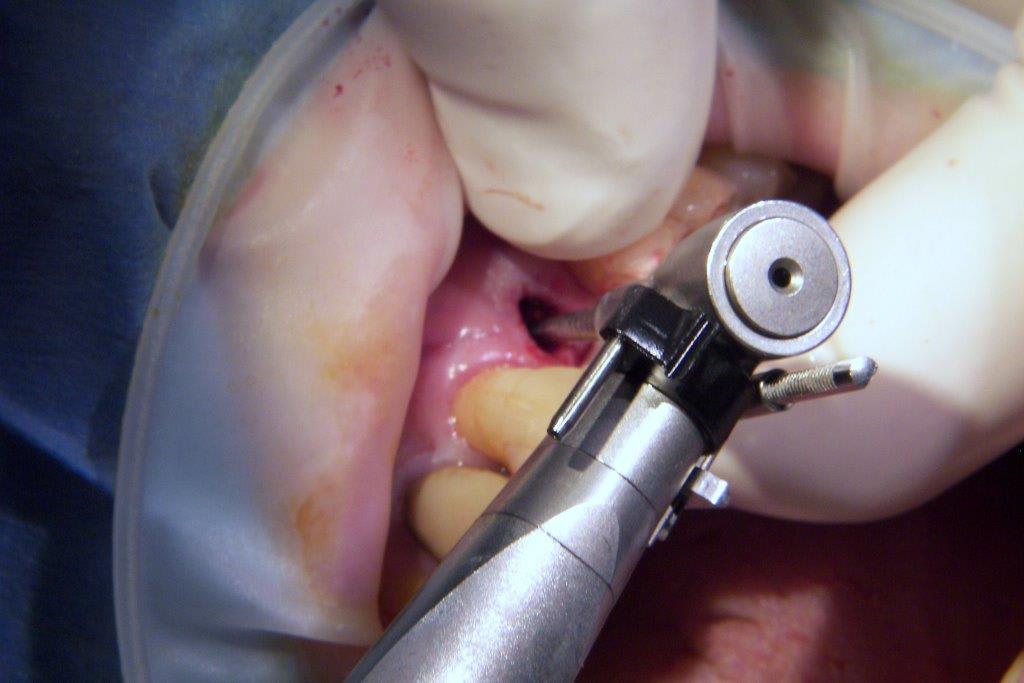

pour ceux que ça intéressent, une petite utilisation d'expansion de la paroi palatine, sur une avulsion d’incisive(racine fendue). toutes mes excuses pour la mauvaise qualité des photos.